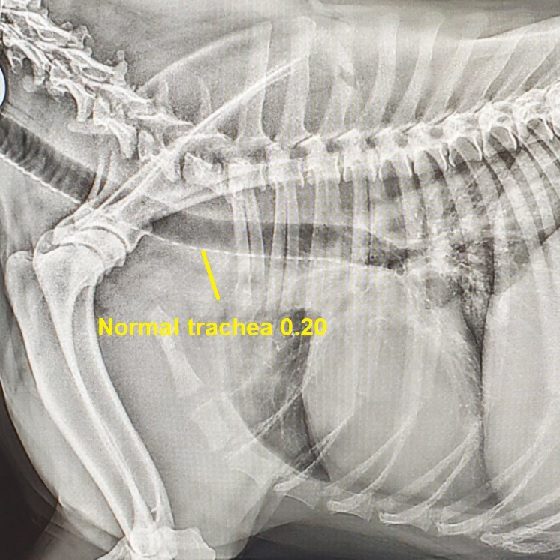

Every airway correction patient carries some risk of poor recovery, some potentially needing a tracheotomy tube to help them breathe post surgery, and potentially even dying post surgery. This risk increases with age, noise and other potential conditions such as laryngeal collapse, redundant pharyngeal mucosa and hypoplastic trachea. Miki had a significant hypoplastic trachea. You can see the size of his trachea here compared to normal dogs.

A normal trachea is 0.20, a grey area one is 0.16 to 0.20, and a hypoplastic one is less than 0.16.

Miki was 0.11. This carries significantly more risk with both getting through life comfortably, and potential complications associated with airway correction. Miki’s owners had not been made aware of his hypoplastic trachea prior to previous vet clinics recommending surgery. In fact, they had not been made aware of this during his long hospital stay some months prior. Not only did we have to increase the odds that Miki may need a tracheotomy tube if he was struggling post surgery, we had to increase the odds Miki may not actually survive surgery as he was older and very severe with his noise.